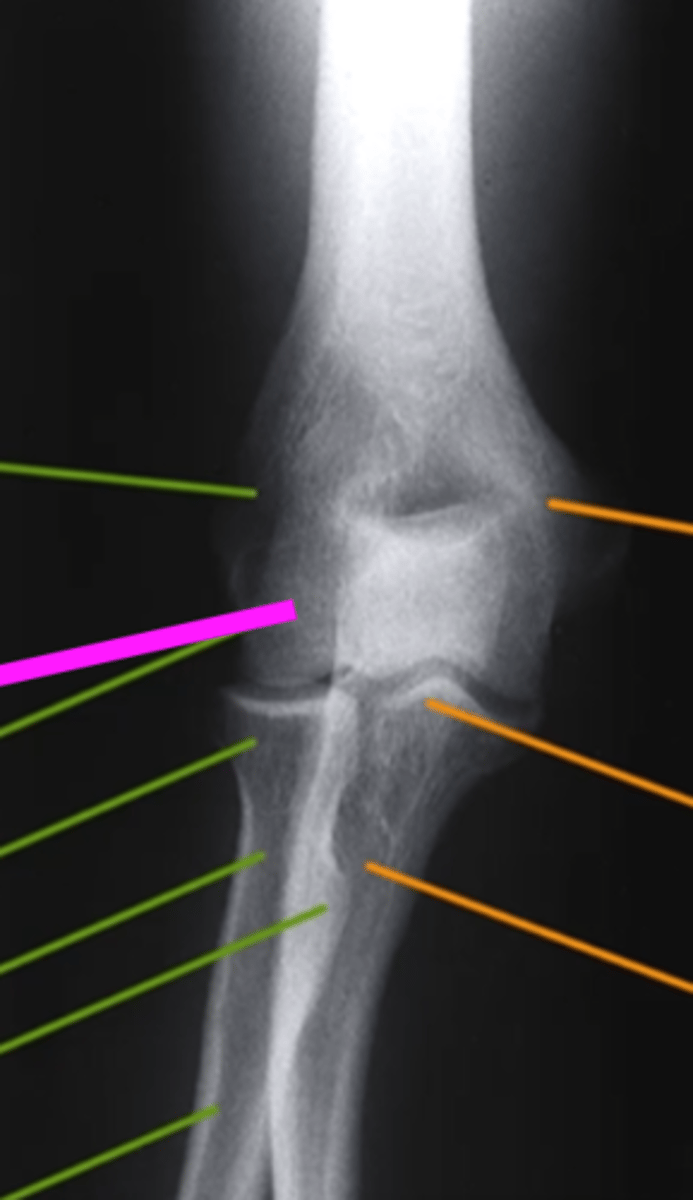

Lateral Elbow

what view is this

humerus

what does the pink line point to?

trochlear sulcus

coronoid process of olecranon

radial head

olecranon process

ulna